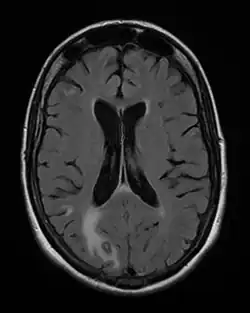

Toxoplasmose

| Toxoplasmose | |